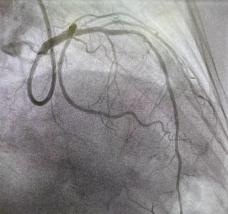

术前冠脉造影图像 术后冠脉造影图像

经过全方位的术前准备后,在心外科、麻醉科、体外循环随时做好抢救性手术的情况下,为患者施行冠脉支架植入术。手术中,心内科Lavarra主任在患者左主干-前降支、回旋支、前降支病变处分别植入1枚支架,整个过程用时80分钟,患者未出现任何不适。术后患者的胸痛症状得到缓解,于3日后出院。